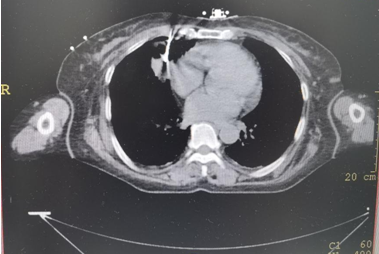

▲上图:穿刺到位

病理报告:低分化腺癌,该患者为双原发肿瘤。